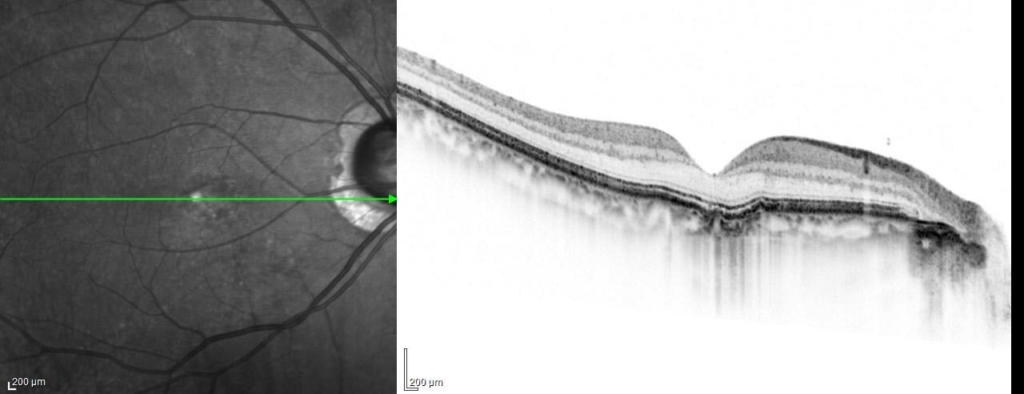

59歳 女性視力 右眼 0.06(1.0p×-3.25=c-2.50A150°) 左眼 0.03(0.2×-3.75=c-1.00A35°)主訴 左眼の視力低下で受診。 乳頭が下鼻側に傾斜し、下方に萎縮(PPA)がみられる。 両眼ともに、後部ぶどう腫staphylomaの上縁に一致して乳頭下縁から黄...